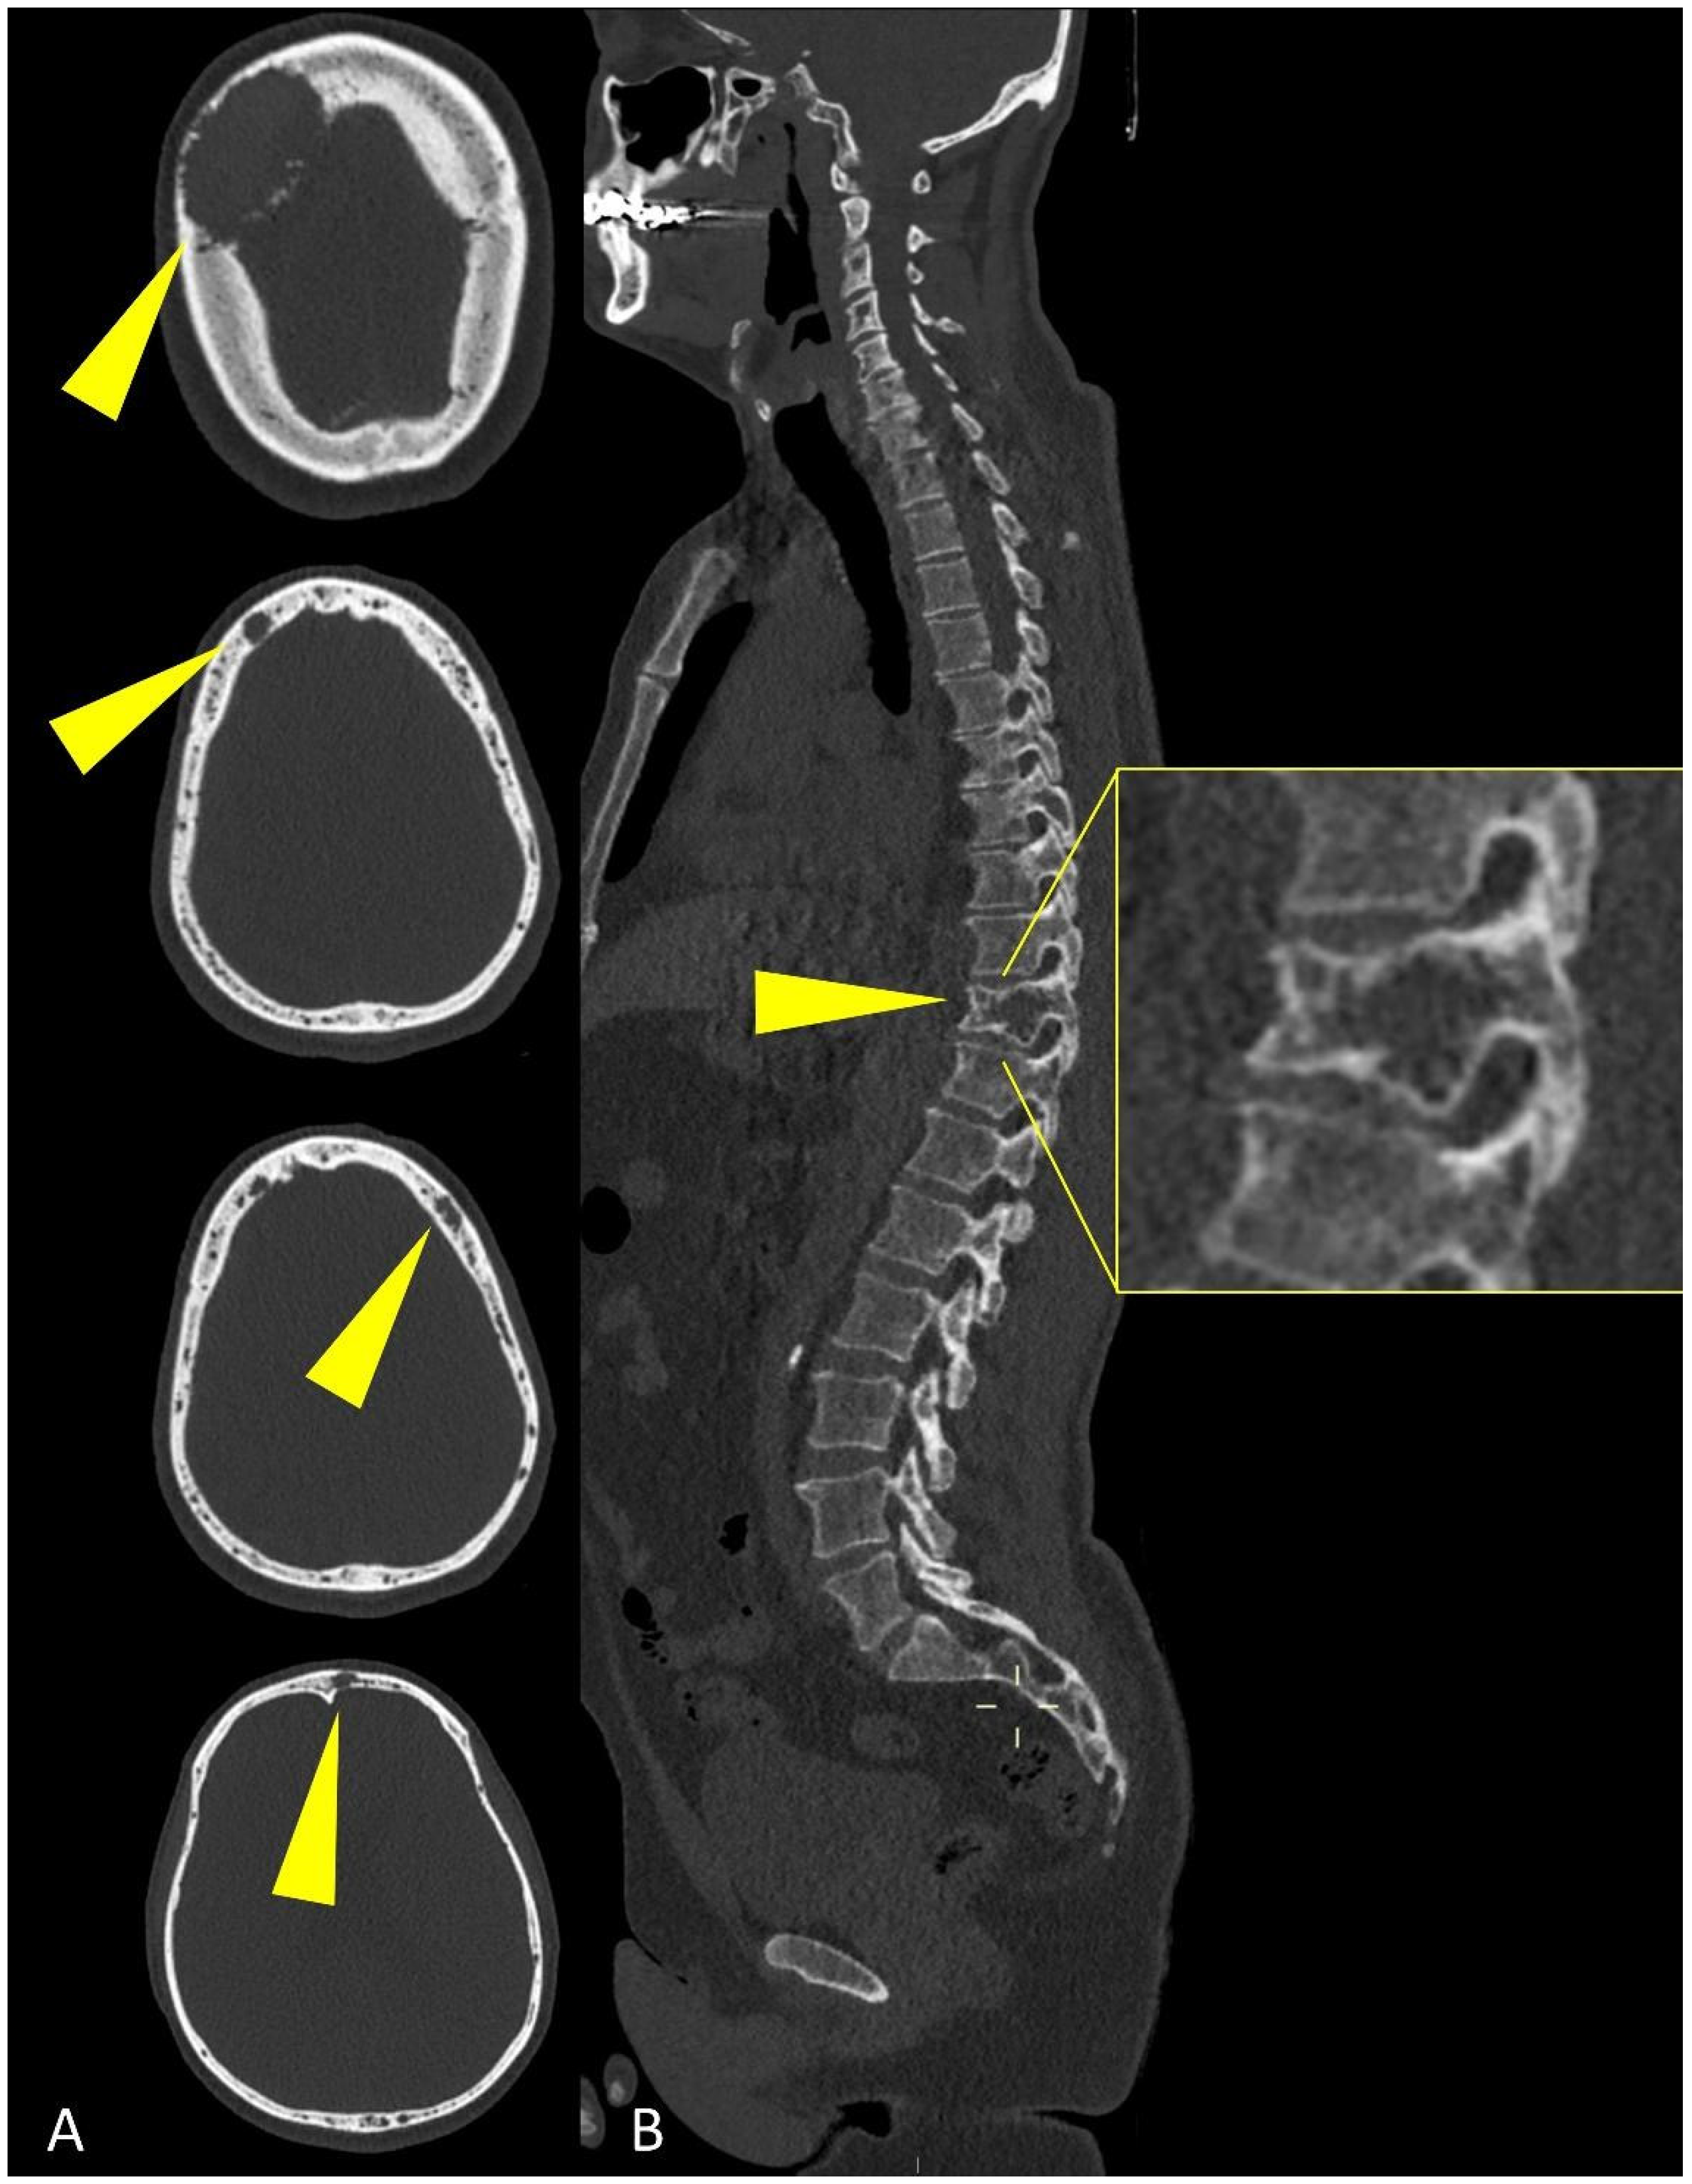

WBLD-CT can assess MM extension better than traditional plain radiograph, because it can show both osteolytic and extra-medullary lesions (Figure 3).

Figure 3.

Multiplanar CT images showing (yellow arrowheads) osteolytic lesions of (A) the skull and of (B) a dorsal vertebra (detail in (B)).

Studies on total-body MRI demonstrated that imaging evaluation of the spine alone in MM patients can miss up to 50% of myeloma lesions, therefore, a WBLD-CT study must include all the parts out of the spine to obtain a correct staging and risk stratification of MM patients [21].